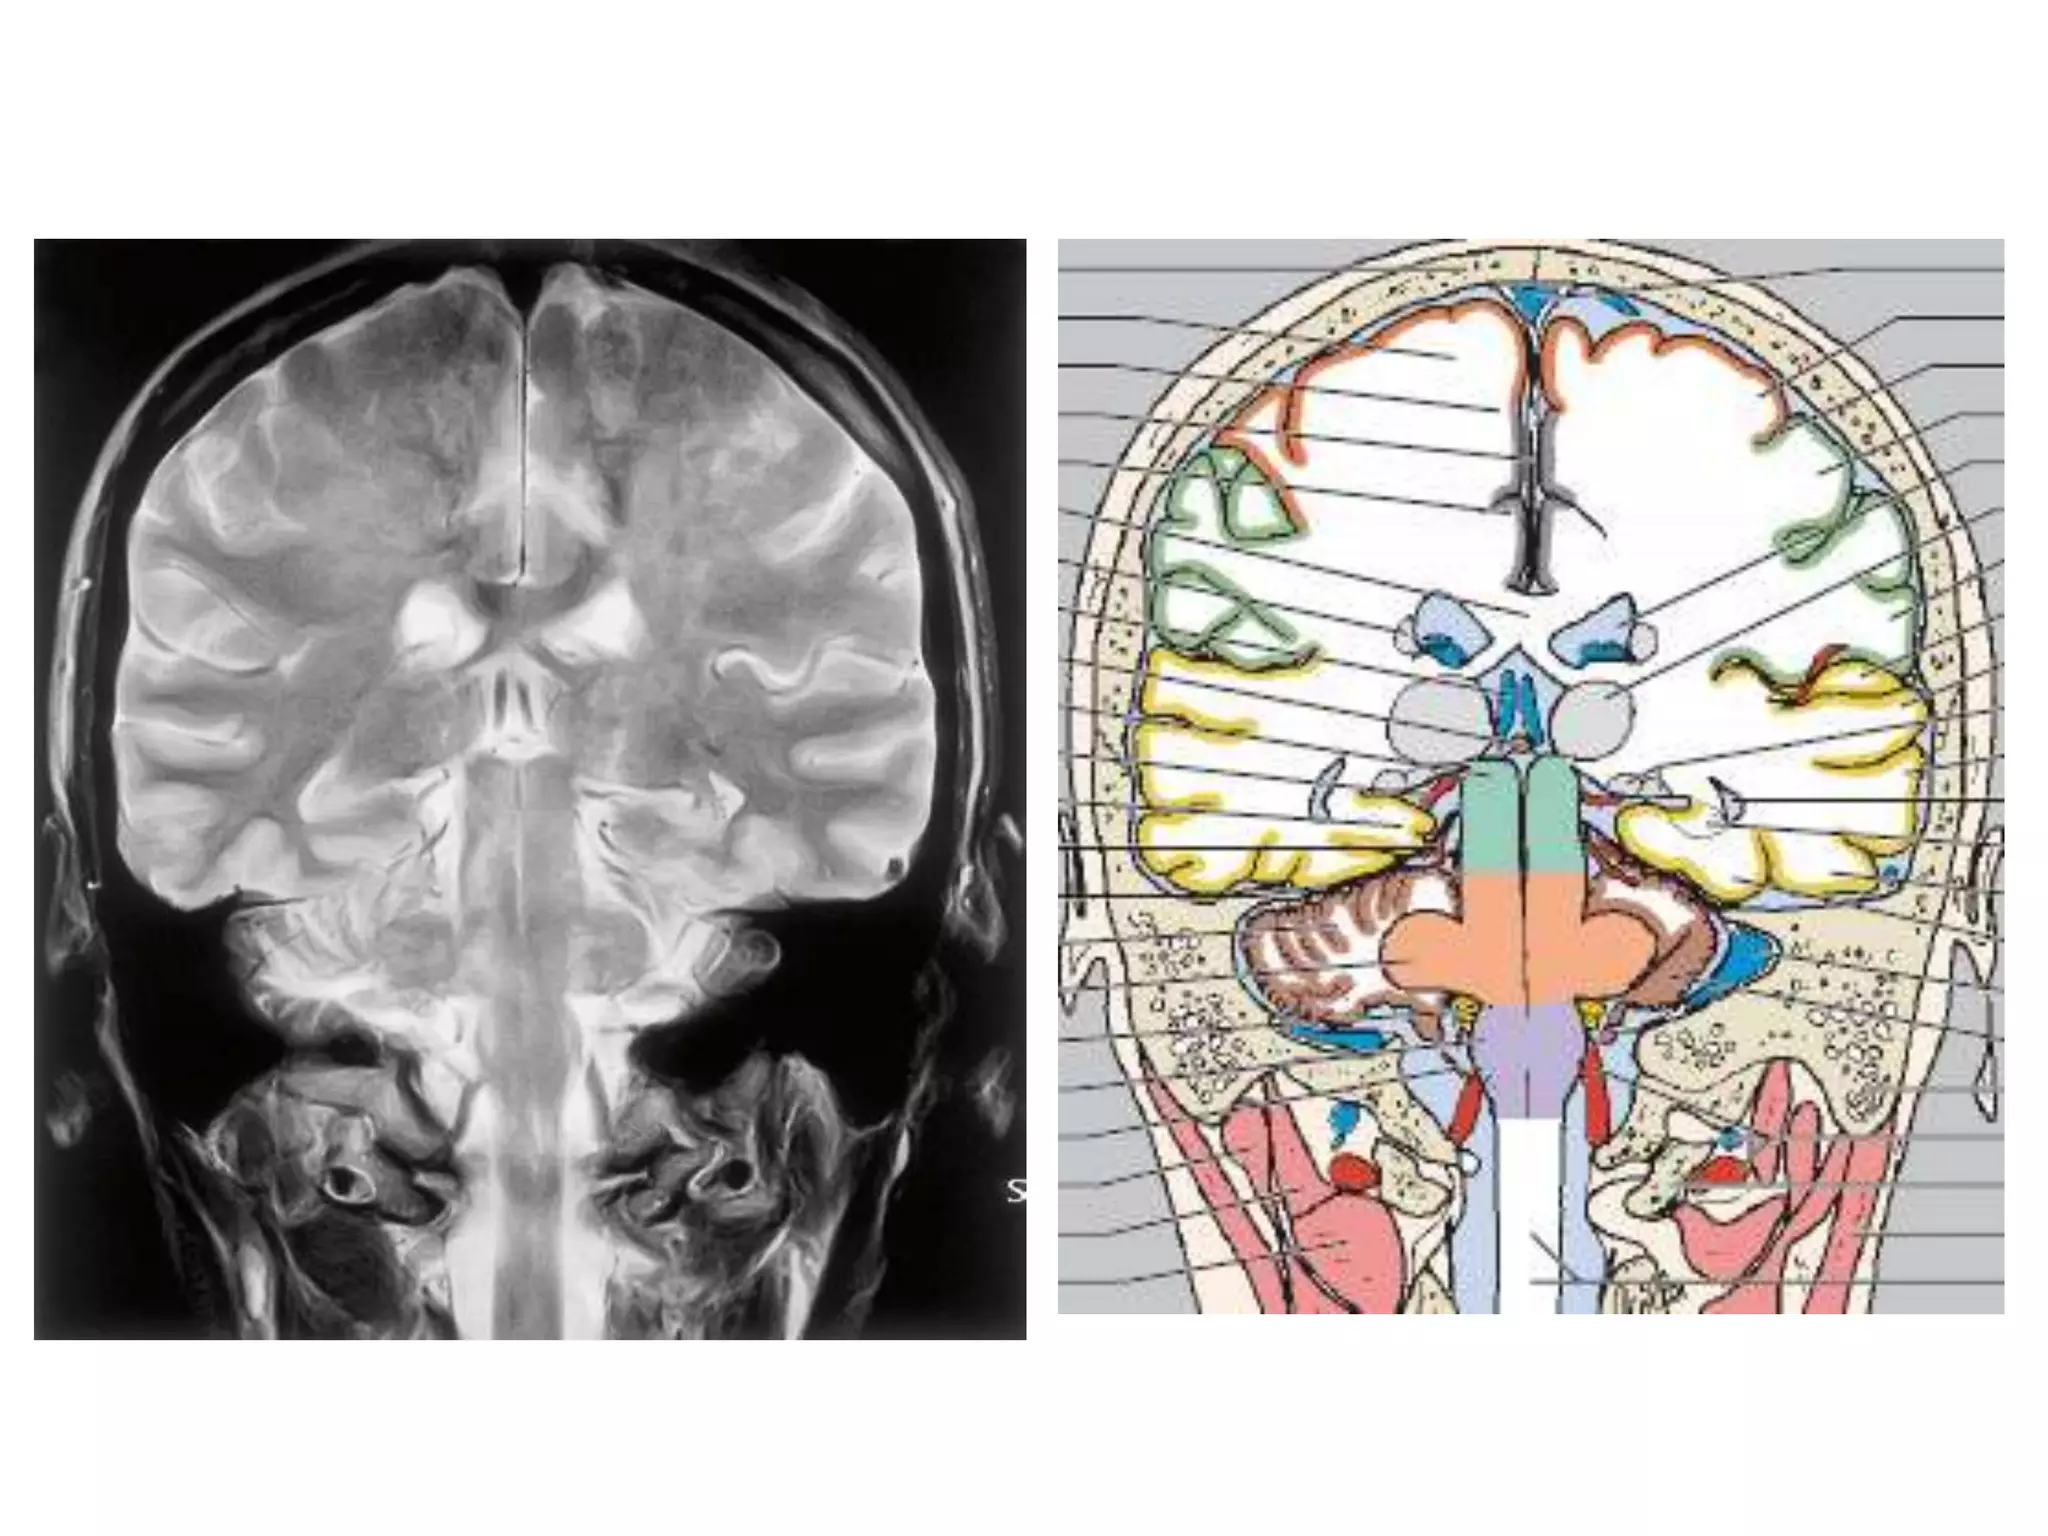

CISTERNS

• Where brain and skull are not closely

apposed, arachnoid and pia separate – and form

cisterns .

• Mainly present at base of brain, around brain stem and

free edge of tentorium.

1.   Posterior fossa cisterns

2.   Basal cisterns

3.   Mesencephalic cisterns

4.   Lateral superior cisterns

POSTEROR FOSSA CISTERNS

1. Medullary cistern : antr. to medulla

VA, spinal A, 12th nerve

2. Pontine cistern : b/w pons & clivus

vertibrobasilar A, AICA & SCA origin, 6th nerve

3. Cisterna magna : b/w medulla & postroinfr. cerebellum

PICA, 9th 10th 11th cranial nerves

(Triangular in saggital section)

4. Supr. cerebellar cistern : b/w tentorium & cerebellar H

SCA, supr. vermian veins.

5. CP angle cisterns : bounded by cerebellum, pons and

tentorium.

AICA, 5th 7th 8th cranial nerves

SUPRASELLAR / BASAL CISTERNS

1. Interpeduncular cistern : b/w Cerebral peduncles

Basilar A, thalamoperf. A .

2. Chiasmatic / Suprasellar cistern : above sella

ICA, MCA & ACA origin, P comm. A,

antr. Choroidal A; prox. basal V of Rosenthal;

optic chiasma & tract; hypothalamus, infundibulum.

(extends from infundibulum to postr. surface of frontal

lobe and lies b/w uncus on either side.

Contains circle of willis and so SAH seen)

MESENCEPHALIC CISTERNS

1. Ambient cistern : surrounds mid brain. Connects

Suprasellar, pontine & quadrigeminal cisterns.

PCA, BA, SCA, 6th cranial nerve .

2. Quadrigeminal cistern : behind pineal & Q plate

Connects ambient and supr. cerebellar cisterns.

Pineal gland, postr 3rd ventricle, V of Galen, V of Rosenthal.

3. Velum interpositum : above 3rd ventricle; below fornix

& C.callosum (antr. continuation of Quadrigeminal

cistern)

Internal cerebral V, Choroidal arteries .

LATERAL SUPERIOR CISTERNS

1. Sylvian fissure : b/w insula & opercula.

connects medially with suprasellar cistern

MCA, supr. middle cerebral V.

2. Convexity subarachnoid space

contains cortical arteries and veins.